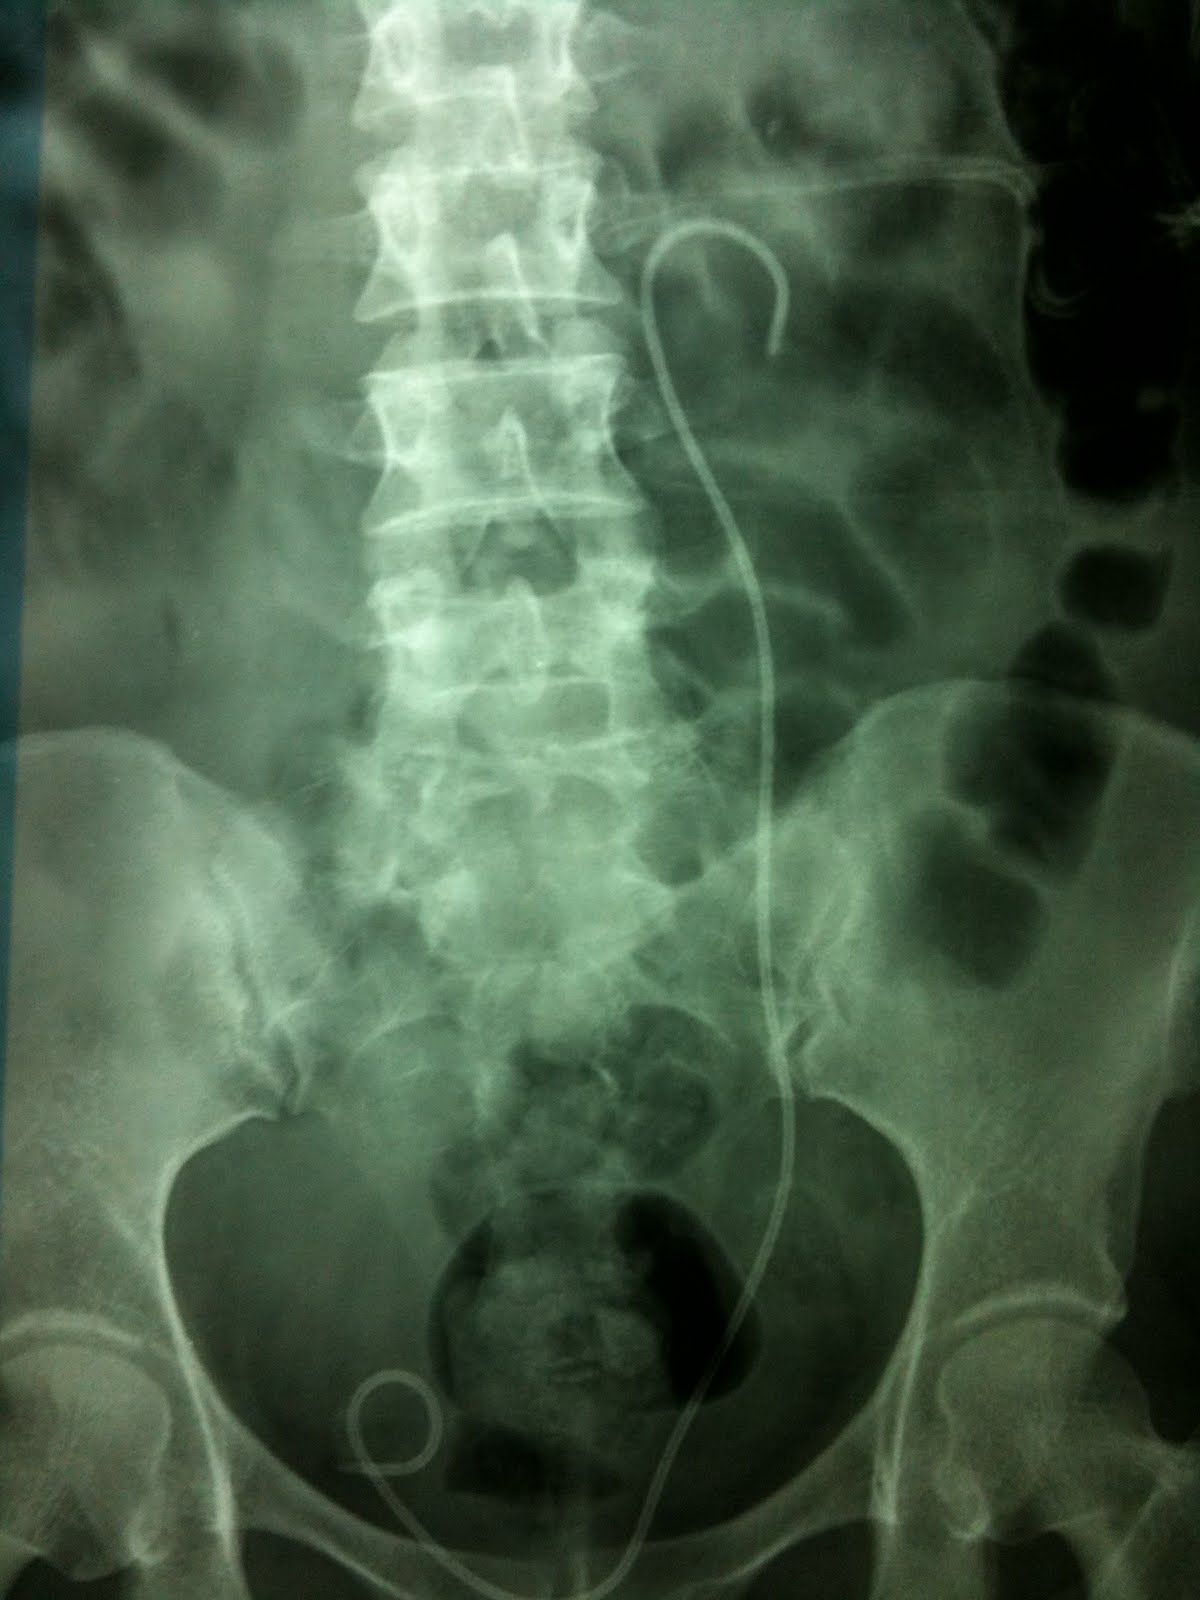

Staghorn Calculus

Staghorn calculus in patient with recurrent fevers, hematuria and flank pain. Radiology Horn Calculus Definition Staghorn calculi are branched stones that occupy a large portion of the collecting system. Staghorn calculi are large branched stones that in continuous integrity fill the renal pelvis and branch into two or more of the. Staghorn kidney stones are a type of large urinary calculus, or stone, that takes up a large portion. Typically, they fill the renal. Staghorn. Horn Calculus Definition.

Xray of kidneys (12 May 2008) showed stag horn calculus in left kidney. Download Scientific Horn Calculus Definition Typically, they fill the renal. Staghorn calculi are the only type of renal stones more commonly observed in female patients as a result of their association with. Staghorn calculi are branched stones that occupy a large portion of the collecting system. Staghorn kidney stones are a type of large urinary calculus, or stone, that takes up a large portion. What. Horn Calculus Definition.

Xray showing large leftsided stag horn calculus, with a second... Download Scientific Diagram Horn Calculus Definition Staghorn calculi are complex renal stones that occupy the majority of the renal collecting system. Staghorn kidney stones are a type of large urinary calculus, or stone, that takes up a large portion. Staghorn calculi are branched stones that occupy a large portion of the collecting system. Typically, they fill the renal. What are staghorn kidney stones? Upper urinary tract. Horn Calculus Definition.